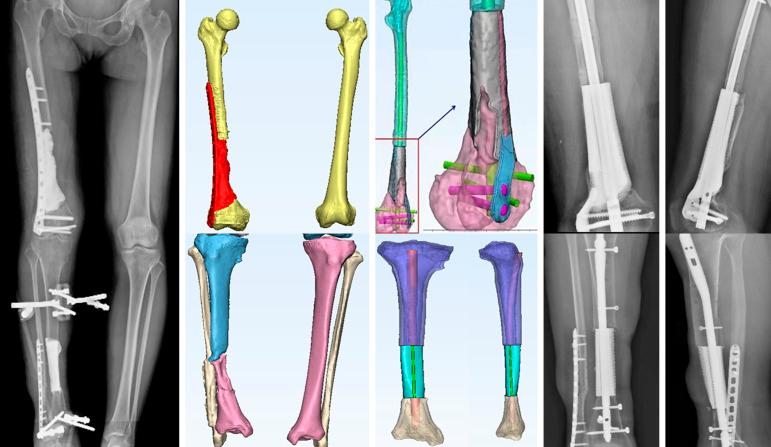

This study reported the case of a 42-year-old woman with traumatic ipsilateral critical bone defect of right femur and tibia after a motor accident. Three-dimensional (3D) printed porous titanium scaffolds were innovatively used to reconstruct this challenging situation. The initial stability was safe enough for early exercise and partial weight bearing. The 26-month follow-up showed osseous integration of the prosthesis-bone interface with short-term satisfactory clinical result.

本研究报告了一例车祸后右侧股骨和胫骨同侧严重创伤性骨缺损的 42 岁女性病例。创新性地使用了三维(3D)打印多孔钛支架来重建这种具有挑战性的情况。初始稳定性足以确保早期运动和部分负重的安全性。26 个月的随访显示假体-骨界面具有骨整合,短期临床效果满意。